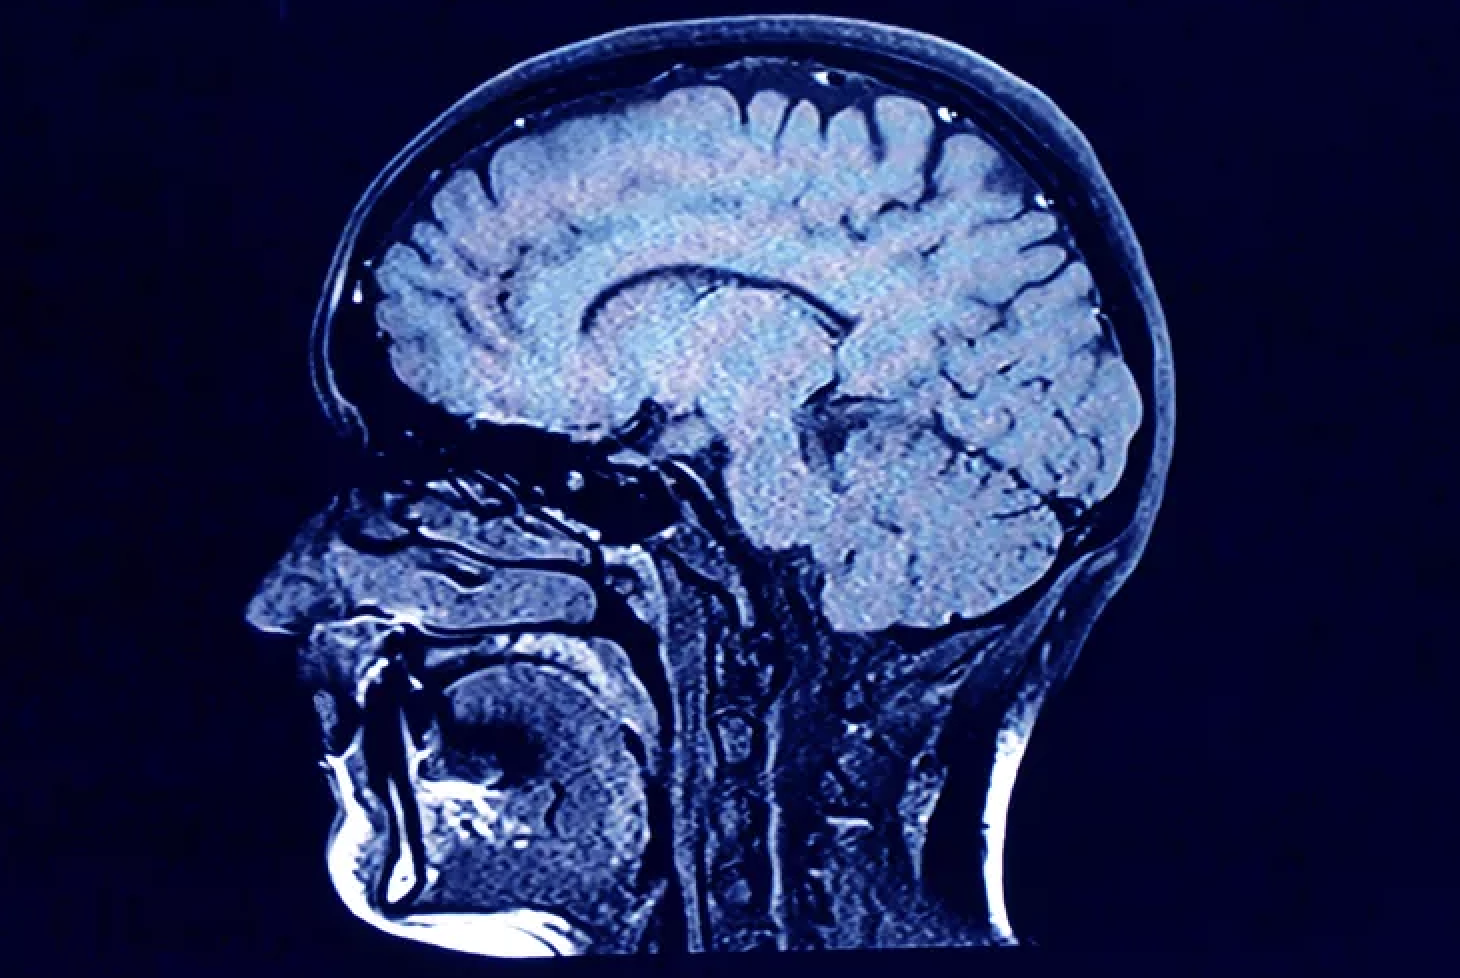

Science explains how things work but not always why they work and this has been especially true in researching human behavior. For example, the phenomena of “connection” or “pure consciousness” achieved in meditative states or with psychedelic interventions such as Ketamine is difficult to describe because of the ineffable quality of the experience. Thanks to functional magnetic resonance imaging (fMRI) technology, researchers can now create pictures of what they’ve been unable to express in words.

Developed in the 1990s, fMRI technology allows researchers to study the human brain, even in the process of activation, illuminating structural changes that occur when brains are absorbed in tasks, as well as when they are not. It was assumed that upon completion of a task the resting brain would enter a somewhat dormant state, but with advanced technology researchers discovered that upon task completion, certain areas of the brain “light up” and become more awake. This state is referred to as the Default Mode Network (DMN), the brain regions that are active when a person is not focused on external stimuli, but engaged in repetitive self-generated thought, such as autobiographical cogitation. It is the ongoing message about what we can, should, and are likely to do. This network of brain regions allows us to reflect on what we have done, and how we feel and think, as well as how we think others feel and think about us. It is reflexive, instantaneously activating when the mind completes a task, and can be altered by activities such as meditation or taking medication. The DMN is “online” even before conscious interest develops, but not before nine months of gestation. Interestingly, it is not present in premature newborns.